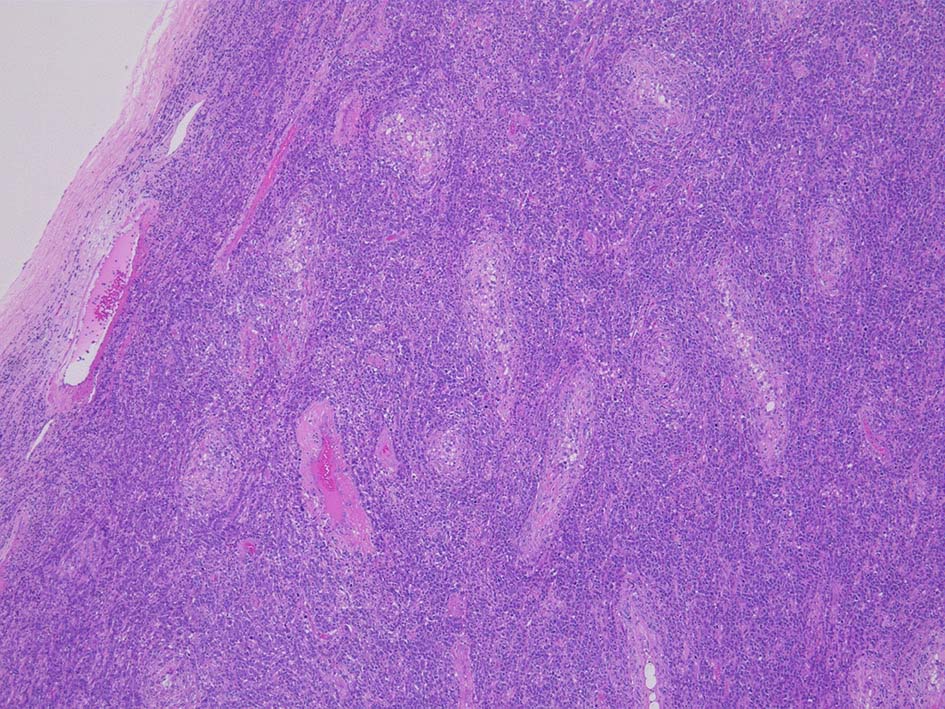

光顕所見; リンパ腫により, 少なくとも一部の領域の精細管が消失する. 末梢の領域では精細管の間質にリンパ腫細胞が浸潤する. ほとんどの場合、腫瘍細胞は精細管に侵入, 精細管の周辺を占め、生殖細胞とセルトリ細胞を中央に変位させるか, または精細管を完全に占拠してしまう.

1/3の症例では硬化像を示す.

腫瘍内に壊死が認められる. 異型リンパ球の密な増殖により精細管は消失している.

増殖巣では精細管は消失, 萎縮. 腫瘍境界部での浸潤所見がある.